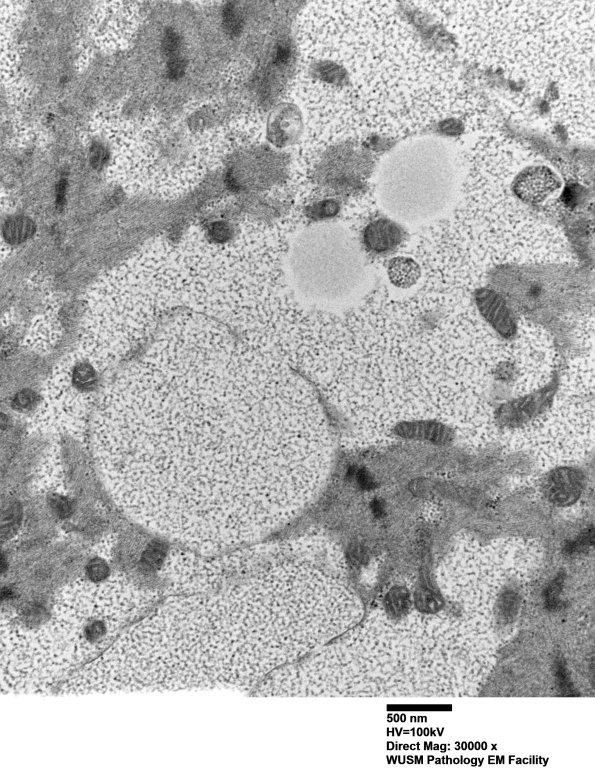

Washington University Experience | METABOLIC | Pompe Disease | 5D8 Muscle (Case 5) EM018 - Copy

The contents of this muscle fiber are complex, distort the sarcomeres and also include lipid collections. (electron micrographs)